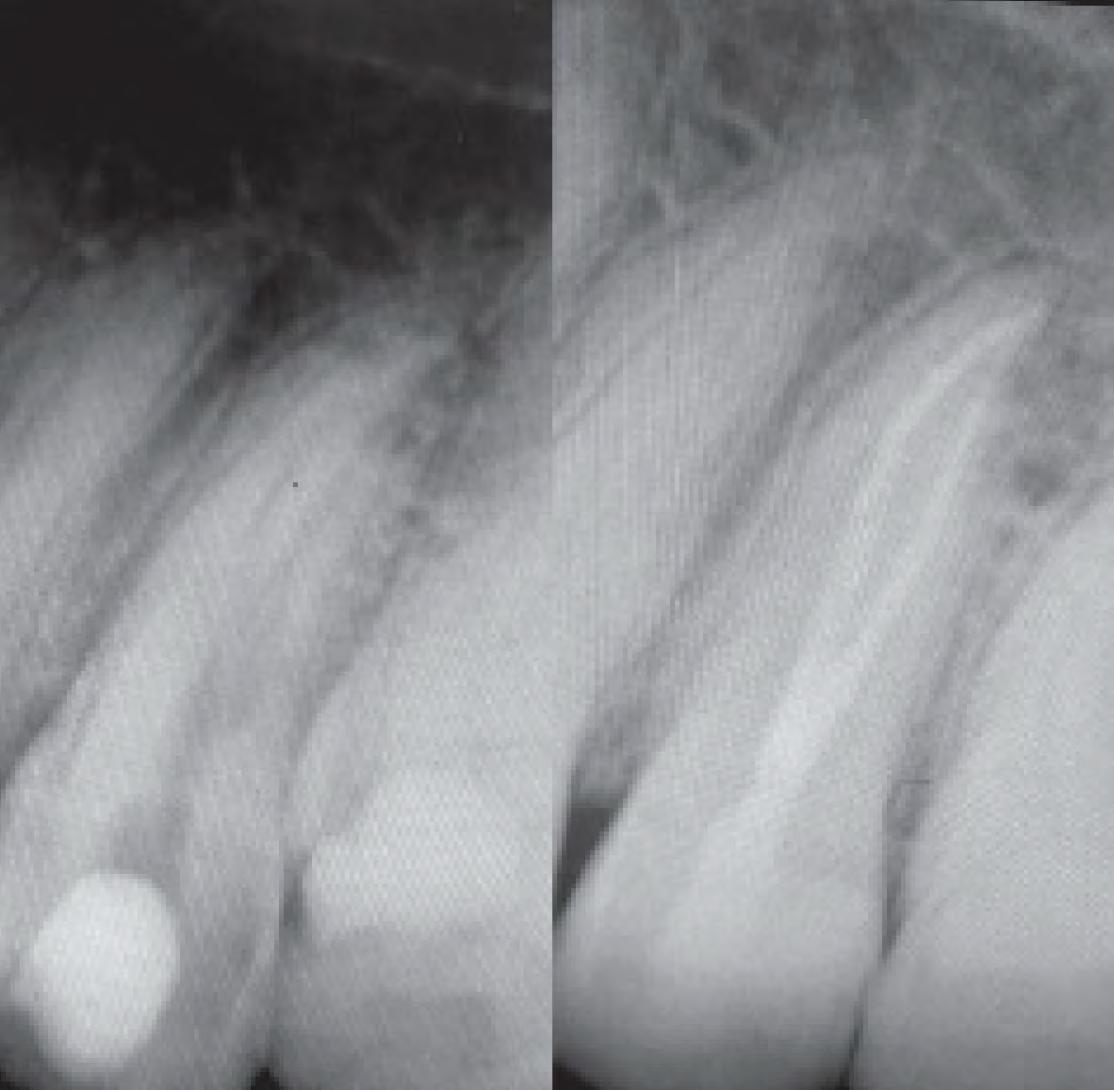

Thanks to the flexibility and ease of use offered by EdgeOne Fire files, I completed this root canal rapidly and safely. Preop and postop images taken 4 months apart display signs of successful healing and an absence of a fistula. I think these files are great tools that every clinician should have.

Preop vs. Postop Radiographs taken 4 months apart

Sean Sunyoto, DDS